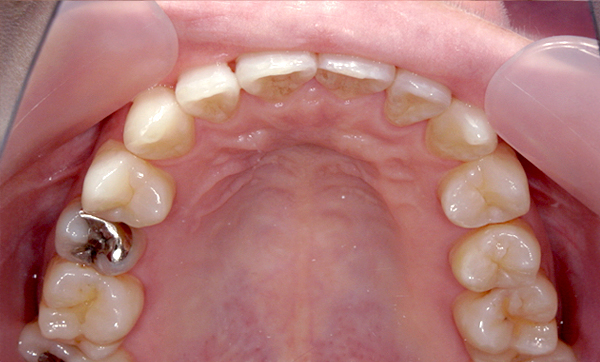

症例_009 「上下の前歯」症例

治療期間:7ヶ月金額:54万円+税20代女性捻転歯一部の反対咬合前歯のガタガタ

Before | After |

---|---|